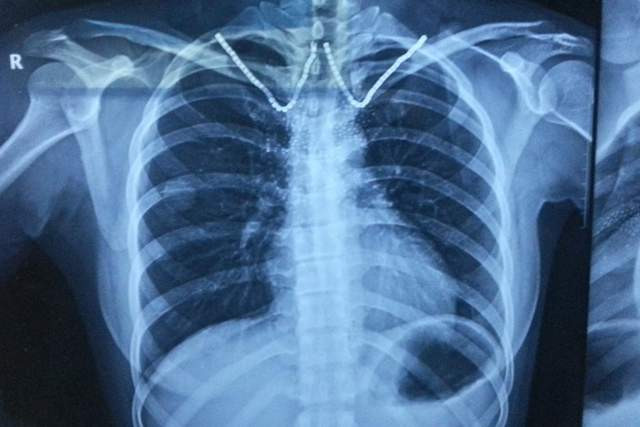

2. 胸部X线或CT查验:匡助放弃其他肺部疾病,并评估肺气肿的进度。